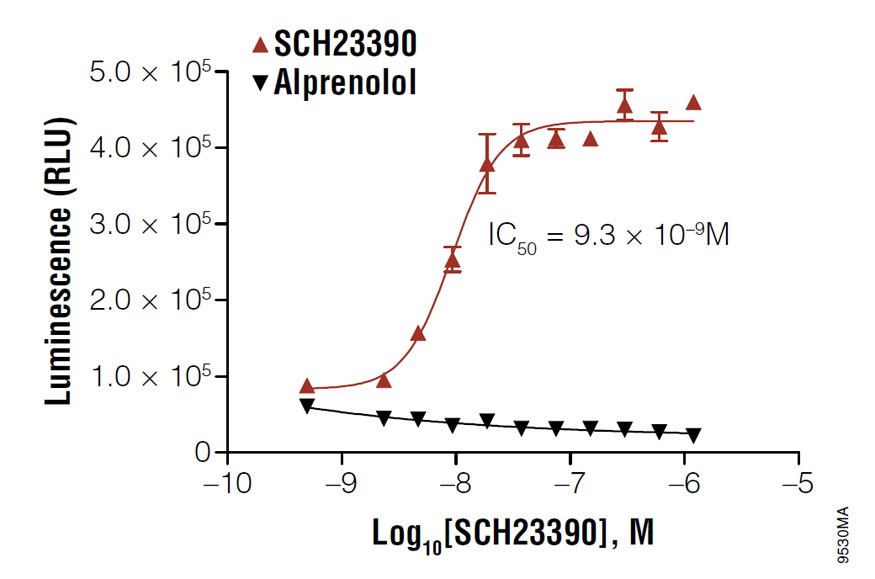

Using cAMP-Glo™ Max Assay to determine the IC50 value of SCH23390 in D1 receptor-expressing HEK293 cells. Cells were treated with the antagonist, SCH23390, in the presence of 100nM agonist, SKF38393.